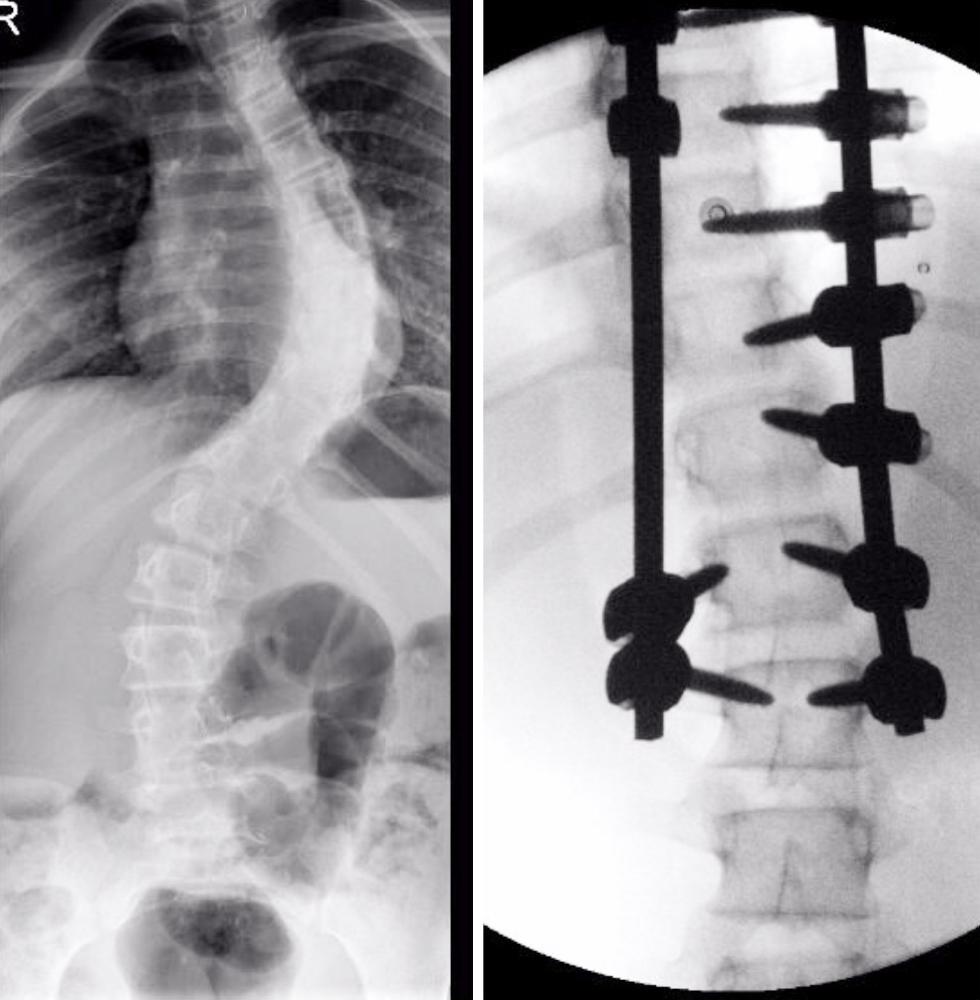

أنهت مدينة الملك سعود الطبية معاناة طفلة تبلغ من العمر 11 عاما، بعد أن كانت تعاني من انحراف شديد في العمود الفقري بلغ 80 درجة، عرقل نموها، وحرمها من المشي بشكل طبيعي.

وأوضح الفريق الطبي، أن الحالة لوحظت من قبل أهلها بوجود انحراف يعرقل نموها، إذ بلغ 80 درجة نحو الجانب الأيسر، منعها من المشي وممارسة الحياة الطبيعية.

وأشار الفريق الطبي، إلى أن العملية تكللت بالنجاح، إذ تم تقويم العمود الفقري، واستطاعت الطفلة النهوض والمشي في ثالث يوم لها بعد نجاح العملية.

صورة الأشعة للعمود الفقري.